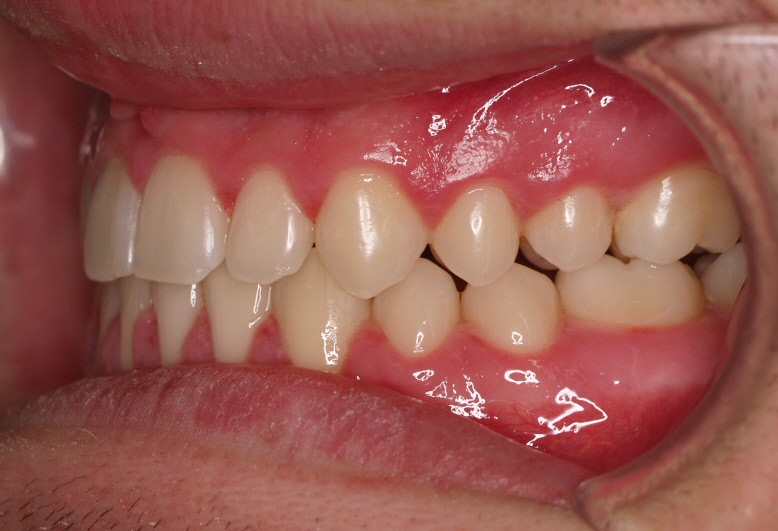

El paciente E.A. acude a nuestra consulta por diastema inferior y ausencia de contactos en los sectores laterales.

El stripping consiste en la reducción interproximal del esmalte entre los dientes posteriores y anteriores, así obtenemos espacio para alinear los dientes apiñados.

Chica de 17 años tratada en 1 año con stripping en los dientes inferiores